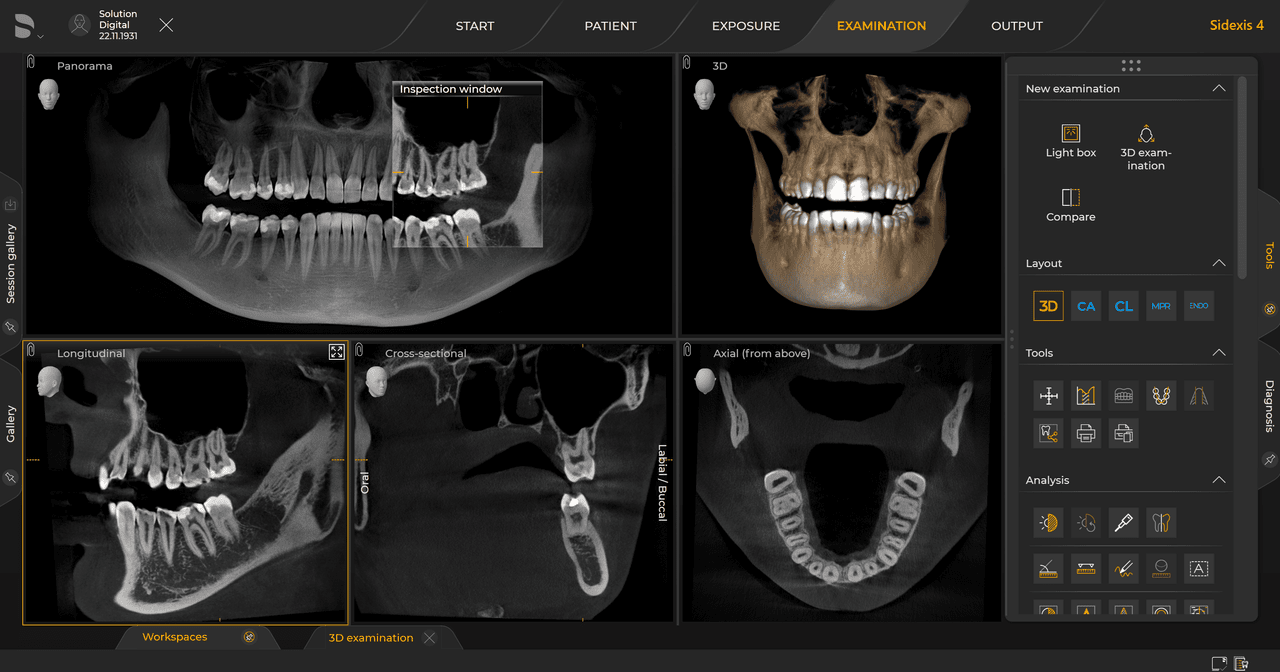

Las unidades de radiología de Dentsply Sirona funcionan exclusivamente con Sidexis 4. Sin embargo, la migración de datos de Sidexis XG a Sidexis 4 es muy fácil. Sidexis 4 permite una experiencia digital completa con las últimas herramientas

Con el modo de dosis baja inteligente 3D, obtiene imágenes 3D en el rango de dosis de una imagen radiológica 2D. En el modo HD (hasta 1400), las imágenes individuales se obtienen durante una única rotación y se convierten en un volumen 3D con hasta 80 μm para imágenes de bajo ruido en alta resolución.